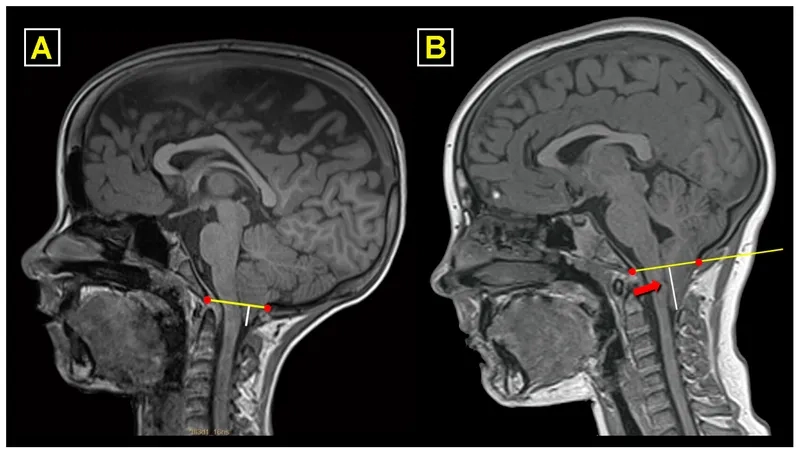

An MRI scan showing what is Chiari malformation